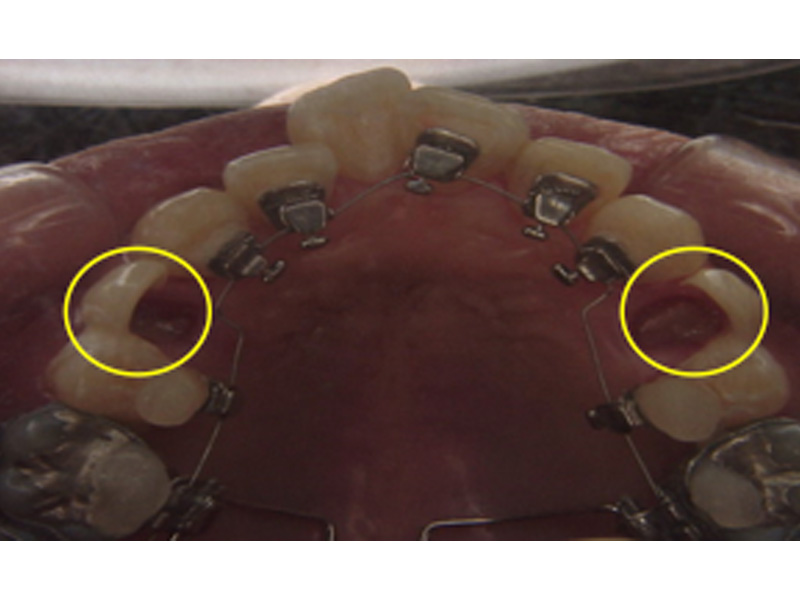

舌側矯正

目立たない

裏側に装置を装着するので周囲の目も気になりません。

衛生管理が難しい

直視しにくいので、歯磨きも非常に難しいです。ペン型や山切りの歯ブラシを使って、時間をかけた丁寧な歯磨きが大切になります。定期的なお口のクリーニングをおすすめします。